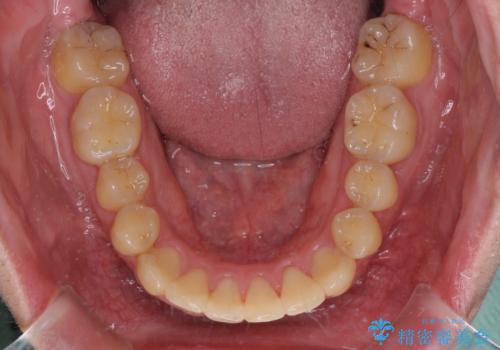

- 上下のデコボコと前歯のクロスバイトを改善したいとのことで来院された患者様です。

マウスピース矯正での自己管理には自信がないとのことで、ワイヤー装置による矯正治療を行うこととしました。

デコボコの程度は強かったのですが、口元の突出感はなかったため、非抜歯矯正としました。